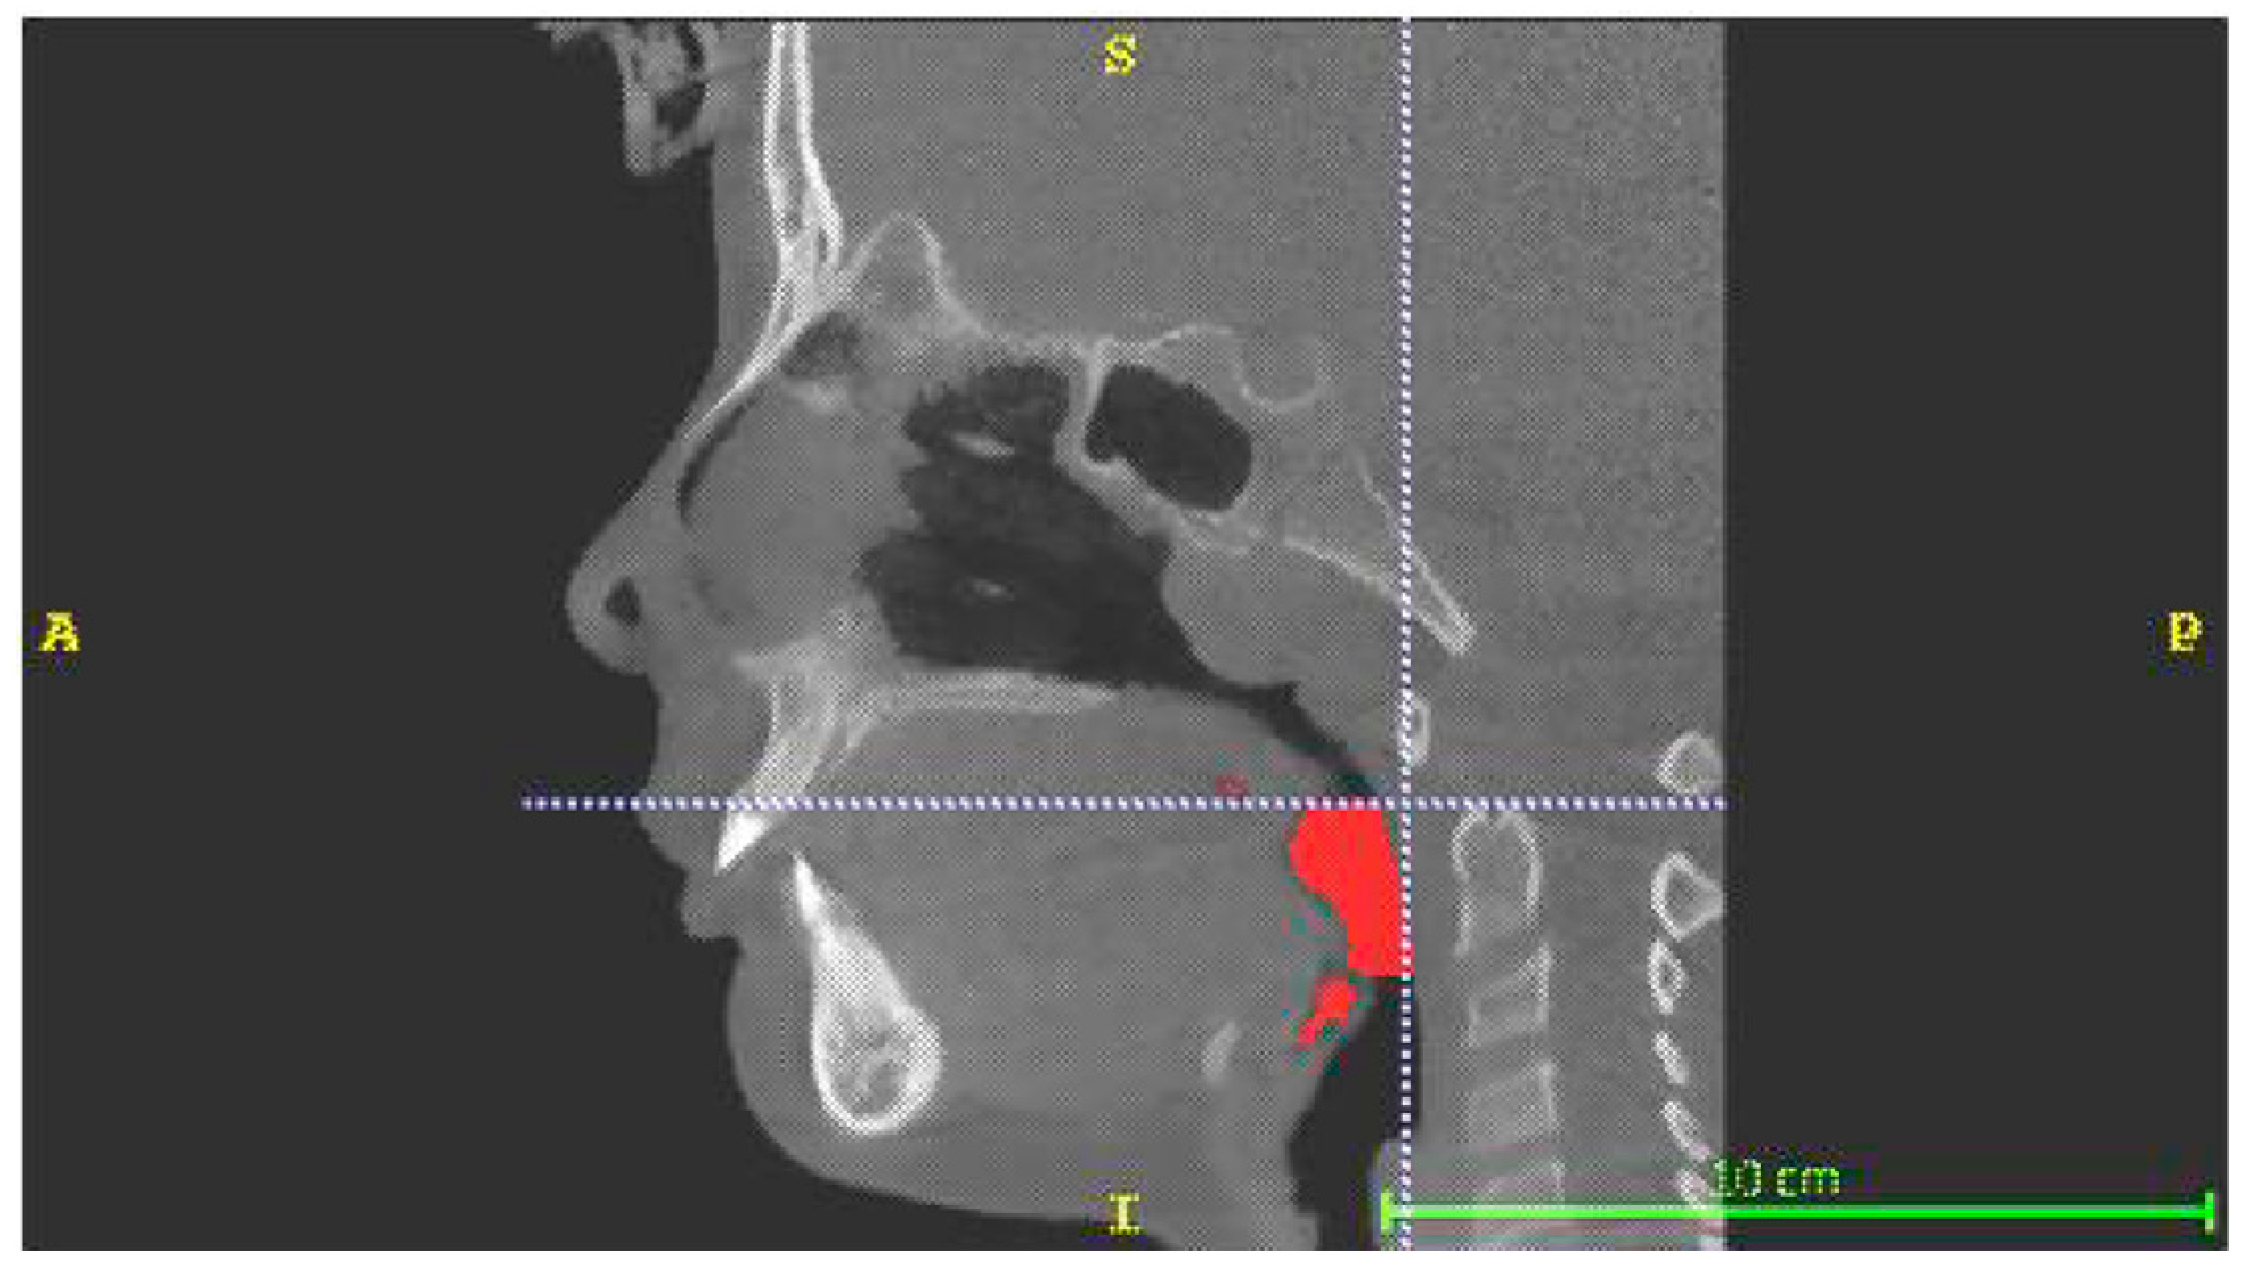

- Retroglossal volume (RGV), limited superiorly by a plane passing through the most postero-inferior point of the soft palate and inferiorly by a plane passing through the most postero-superior point of the epiglottis. This volume also included the volumetric portions facing the oral cavity between the soft palate and the lingual root and between the epiglottis and the lingual root (Figure 2).